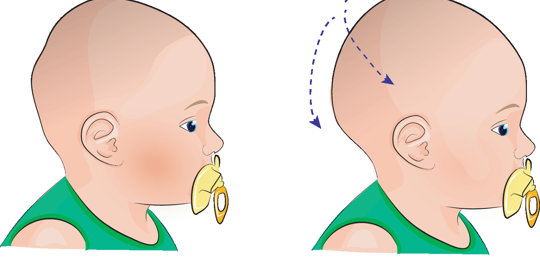

嬰兒斜頭畸形:側睡風險與斜頸症評估